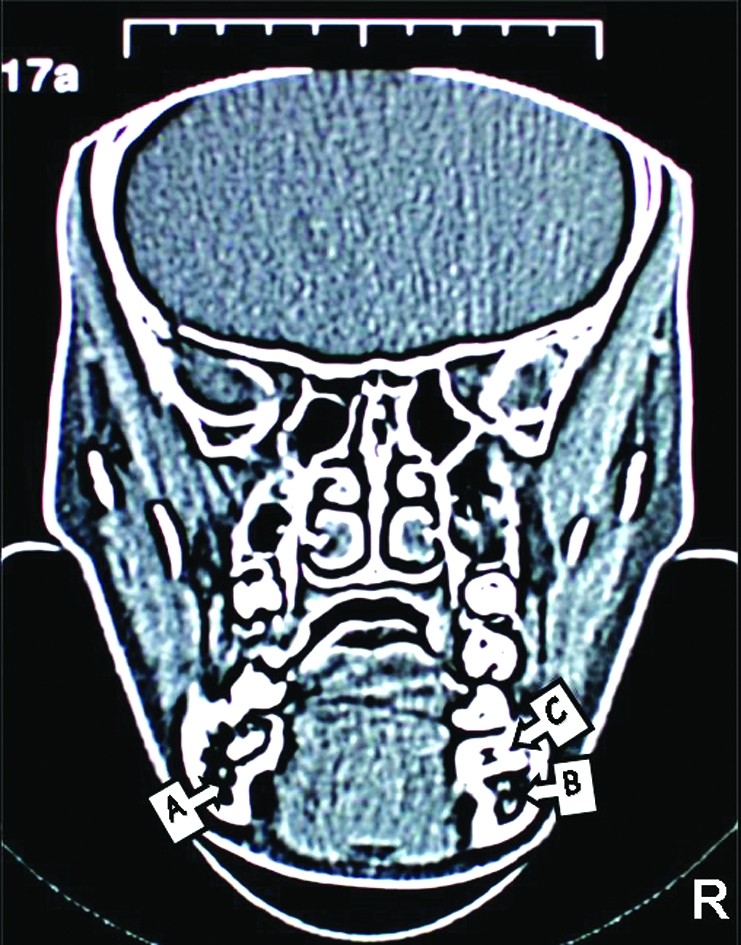

Figure 4.

CT images of the patient. The position of right inferior dental canal can be seen clearly as a dark area but left inferior dental canal cannot be seen due to the impacted second premolar. (A; Right Mandibular Canal, B; Left Mandibular Canal, C; Tipped Right First Molar, D; Impacted Right Second

In order to assess the position of the inferior alveolar canal and the relationship between the canal and second premolar a coronal, CT was taken (Philips Tomoscan, Netherlands). CT scanning of the mandible consisted of 26 slices with a thickness of 3mm and 1mm slice gap. Relationship of inferior alveolar canal and impacted premolar can be observed in Figure 4. Furthermore the amount of bone volume of the involved section and symmetrical section (to compare the bone volume) calculated from the slices on post processing screen of the system. The bone volume was 8.46cm3 on the right side compared to 12.75cm3 on the opposing side which demonstrated that the structural weakness could arise, if molar, premolar and primary second molar were extracted. This could lead to long term problems such as potential pathological fracture of the mandible.

In addition to the plain radiographies a CT was taken, due to the difficulties of locating the inferior alveolar neurovascular bundle in our case, which enabled us to determine the involved area more precisely for ensuring the vital structures are protected. The bone volume was calculated 8.46 cm3 on the right side and 12.75 cm3 on the opposing side from post processing screen of the system. This may imply extensive bone removal is required for extraction of the affected teeth which may predispose mandible to pathological fracture. Besides the possibility of eruption of second premolar was not considered in our case Premolar) as the tooth had curved root shape. Moreover, CT images revealed that mandibular nerve passes the impacted teeth in a very close proximity. Damage to the inferior alveolar nerve during the process of removal of the impacted teeth is highly likely. Previous reports documented that multiple impacted teeth were only observed with no surgical exposure or orthodontic traction due to the risk of extensive bone loss after surgical intervention.1,23